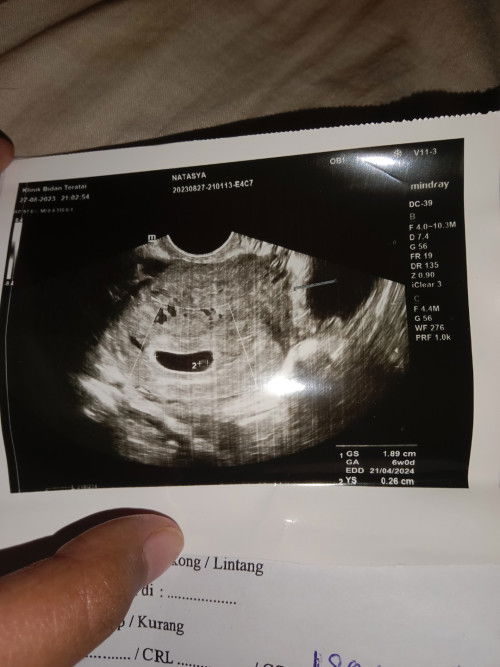

Bun mao tanya kmren bln Agustus USG apakah ini sudah ada janin?

In syaa Alloh ada Bunda. Ada tanda bulat di bawah itu. Jaga kesehatan, makan makanan sehat bergizi. Barokallohu fiikum

dokter blg sudah ada cmn dsruh banyak makan, khawatir bund tkutnya ga berkembang hehe